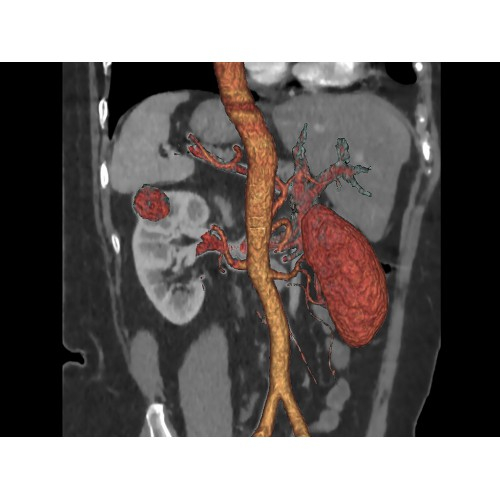

Современный КТ аппарат GE Optima CT520 – это инновационное оборудование для точной и быстрой диагностики. Он сочетает в себе передовые технологии, надежность и удобство использования, что делает его востребованным в медицинских учреждениях различного профиля.

• Высокое качество изображения благодаря усовершенствованной системе реконструкции данных.

• Широкая область применения: от неврологии до кардиологии и онкологии.

КТ аппарат GE Optima CT520 используется для диагностики широкого спектра заболеваний:

• Неинвазивная оценка состояния коронарных артерий.

• Диагностика атеросклероза и других сердечно-сосудистых патологий.